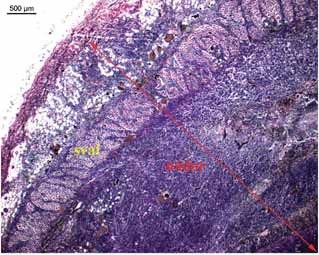

Nádor se víceméně šíří radiálně a uchovává si kruhový čí oválný tvar, jehož rozměry jsou 4. den menší než 1x1x1cm, 12. den 20x31x8 mm a 20. den 54x54x21mm. Hustota cév byla orientačně změřena ve světelném mikroskopu v programu Leica. Četnost cév se zvýšila mezi 4. a 14. dnem 1.44 krát na jednotku plochu (viz obrázek 4 a 5). Celkový průřez cév (jejich souhrnná plocha) je předmětem dalšího zkoumání.

Obrázek 4 - Histologický řez 5. den po aplikaci nádorových buněk (barvení HE)

Obrázek 5 - Histologický řez 14. den po aplikaci nádorových buněk (barvení HE)